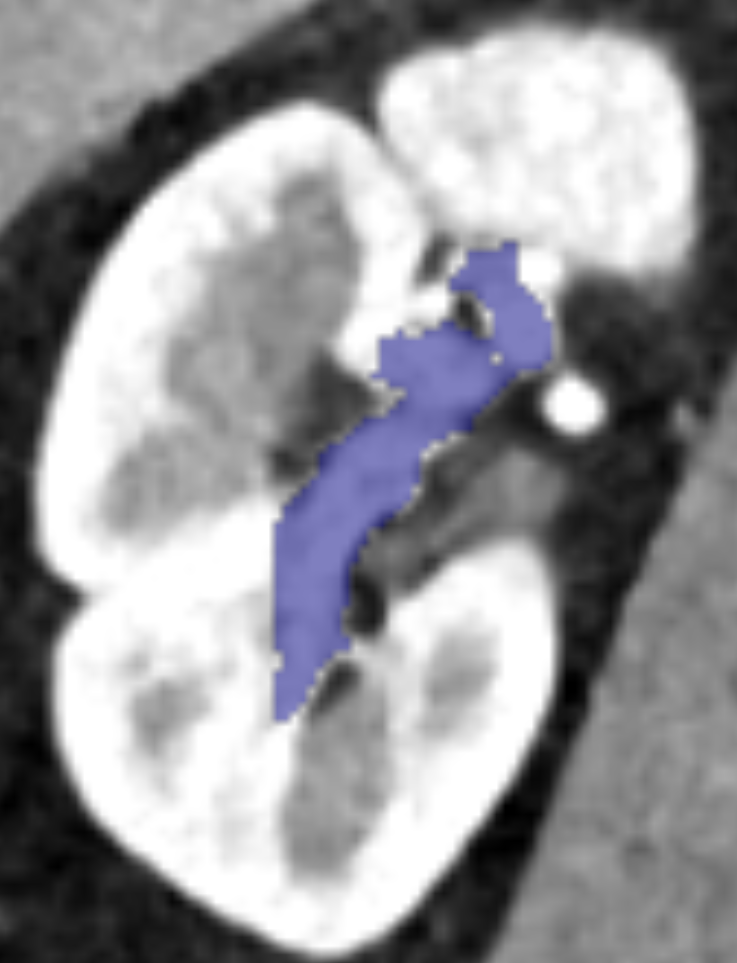

Table 1 summarizes the quantitative results and highlights our network ability to segment both coarse and fine vessels around the kidney. Artery segmentation is the most accurate because all scans are done during arterial phase. This suggests that better vein and ureter segmentations are feasible if venous and waste-out scans are available. The thick aorta boosts artery segmentation F1 score in the whole ROI. In the kidney bounding box, tiny artery vessels become more challenging, and F1 score relatively decreases. The same argument explains vein vessels F1 score. Since arterial scans are used, concealed vena cava penalizes F1 score severely in the whole ROI region. This observation manifests in figure 4, second column. While aorta is easy to segment and boosts F1 score, vena cava is more challenging and thus F1 score degrades.

Figure 4 shows qualitative results and highlights vessels around the kidney. All CT-slices are rendered using soft tissue window–level=40, width=400. Vein and collecting system segmentation are the most challenging. The second column shows a shortcoming case due to a concealed vein. Fine vessels near kidney are the most difficult to annotate. Manually annotating such vessels can be cumbersome and time consuming. Thats why Kid-Net is valuable; its training schema enables fine anatomy segmentation in high resolution CT-volumes, and voids GPU memory constraints.